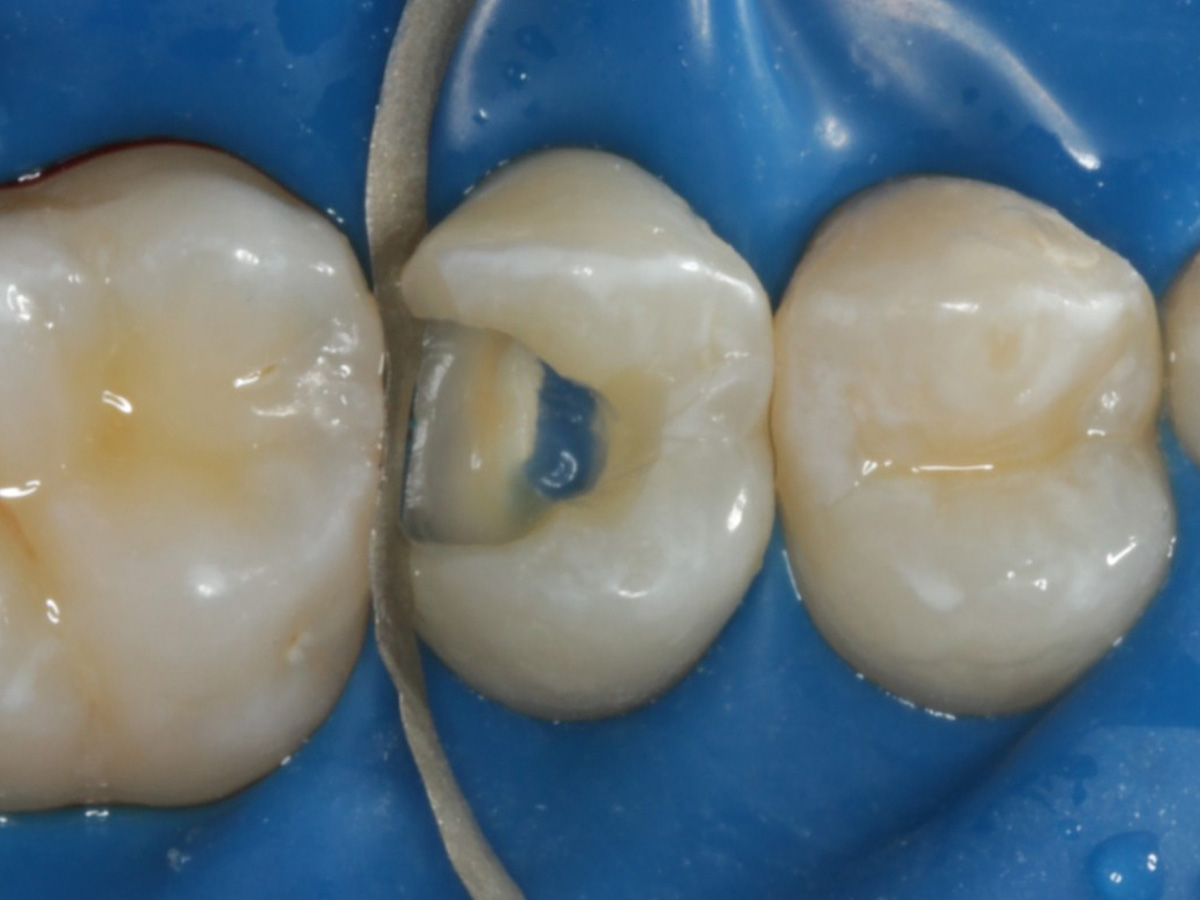

Abbildung 6

Pulpenkavum mit Watte und farbigem Komposit abgedeckt; zuvor Spülung der Wurzelkanäle nur mit NaCl zwecks Nichtgefährdung der Kompositadhäsion